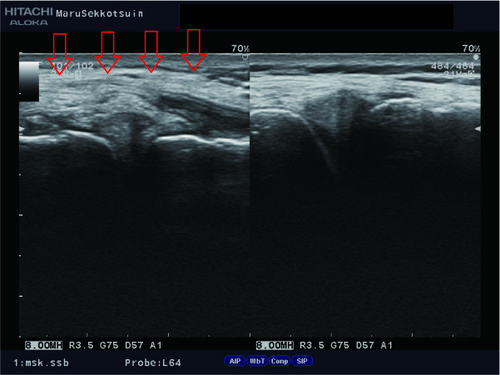

昨日はサッカー中に相手と接触し膝を痛めた方。

内側側副靭帯、内側半月板、前十字靭帯の損傷疑い。

triad2.jpg

この複合損傷は「unhappy triad:不幸の三徴候」と言われ、

膝の構造上、同時に損傷する場合があります。

こちらの患者さんもその兆候が見られ、

しっかりとフォロー&ケア。